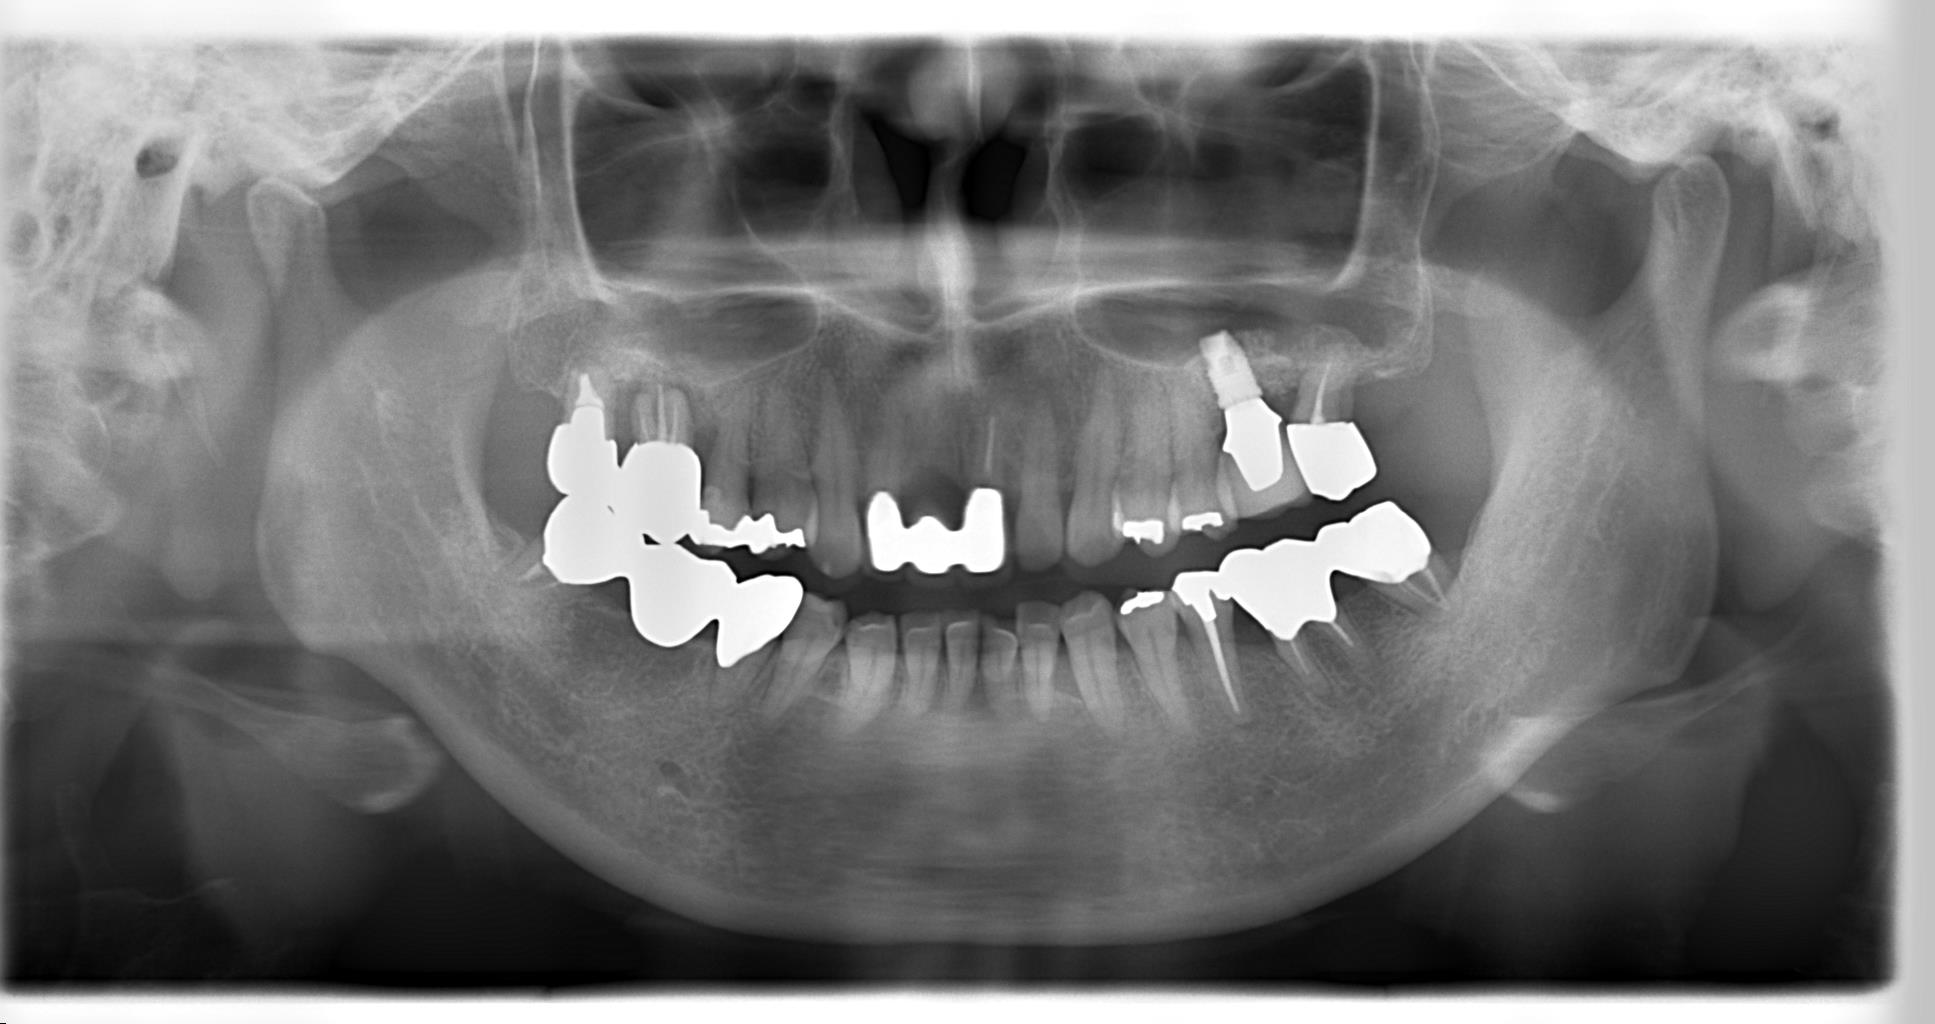

抜歯後にレントゲンとCTを撮影すると、

欠損部の歯槽骨がほとんどなく、上顎の奥歯の上方にある上顎洞(副鼻腔)に近接している状態でした。(上顎洞は空洞です)

インプラントは骨内にしっかり埋入しなければなりませんので、この状態では不可能です。

そこで、頬側から上顎洞粘膜を挙上し、そのスペースに人工骨を移植することにより垂直的に骨を造成する、サイナスリフト(上顎洞底挙上術)を行いました。

サイナスリフト後、上顎洞底の位置が変わっているのがわかります。

そして、移植骨が置換し成熟する期間をおいた後に、十分な長さのインプラントを埋入しました。

サイナスリフトにより垂直的に骨を増やすことができたので、このようなインプラント埋入が可能になったのです。